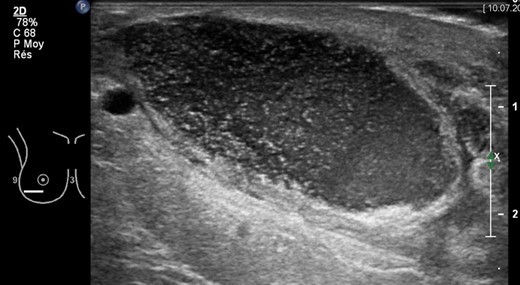

A 36-year-old Caucasian heavy smoker (1 pack/day), with no other comorbidities, presented with bilateral symptomatic breast hypertrophy. Reduction mammoplasty was performed following Thorek's technique [5]. Standard disinfection was performed with antiseptic povidone–iodine and 600 mg of intravenous (IV) clindamycin was delivered at anaesthesia induction. More than 1.1 kg of tissue was retrieved from each breast. Three weeks postoperatively, wound dehiscence associated with discharge was noted on the inferior border of the right breast. Neither redness nor heat was detected locally. The patient was apyrexial with no inflammatory syndrome (WBC count 11 g/l and C-reactive protein 6 mg/l). A smear of the discharge with liponecrosis showed low quantities of P. avidum. No antibiotic therapy was introduced at this moment and dressings with argentic sulfadiazine were prescribed every 48 h (Ialugen-plus, IBSA, Switzerland). Seven weeks postoperatively, a new red and tender induration in between the inferior quadrants of the right breast was noted. Interestingly, the patient remained apyrexial with no inflammatory syndrome. A breast ultrasound (US) showed a 4 × 4 × 15 cm encapsulated collection (Fig. 1). The abscess was drained and bacteriological examination of the purulent fluid revealed a larger quantity of P. avidum. Amoxicillin–clavulanic acid three times/day IV was started as empirical treatment for soft tissue infection. During the IV antibiotic treatment, no differences were seen in blood test parameters; however, a clinical improvement was evident with the discharge steadily decreasing. A control breast US on Day 5 post IV treatment showed remission of the abscess (Fig. 2). Results of antibiogram analysis confirmed the bacteria presence and its sensitiveness to amoxicillin–clavulanic acid. IV antibiotherapy was continued cessation of wound dehiscence (2 weeks), and then switched to oral amoxicillin for 1 month (750 mg three times a day). A breast US 1 month later showed abscess resolution and antibiotic therapy was discontinued. On physical examination, the infection had healed, and no surgical reintervention was needed (Fig. 3).

Right breast ultrasonography (US) showing encapsulated purulent collection (4 × 4 × 15 cm) in correspondence of the lower lateral quadrant, 7 weeks after breast reduction surgery. Abscess drainage was performed under US guidance.